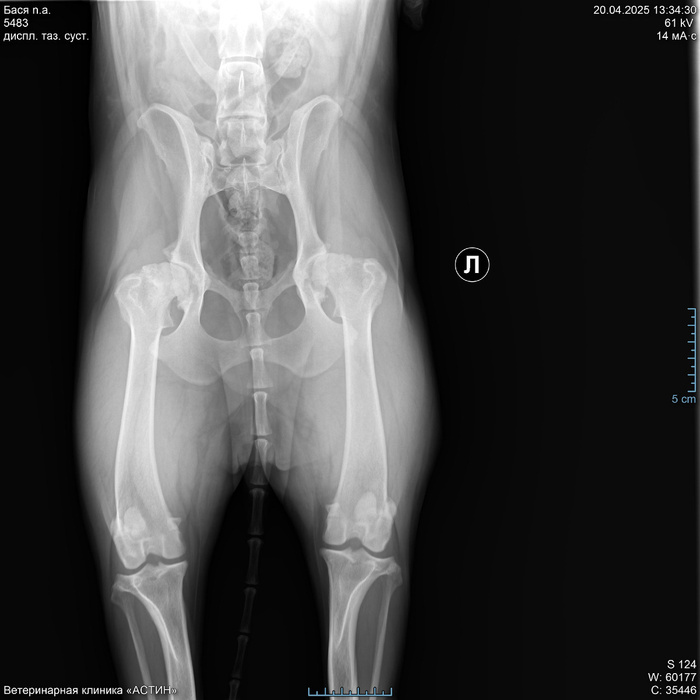

На приеме хирург покрутил и повертел лапы, сделал рентген и сообщил, что ТБС у Баси-то практически и нет. Суставы оба убиты в ноль. Мы, честно говоря, немного обалдели. У нас до Баси был немец и мы знали что такое дисплазия, хотя немец ушел на радугу все же на своих четырех лапах без операций. Но мы думали, что мы знаем как выглядят больные суставы. Оказалось, что вот эта редкая хромота была вполне себе признаком. Тут мы виноваты, конечно, не досмотрели. Ну и хирургом нам были предложены три тактики дальнейшего лечения. Первая - оставить все как есть. Условно - приложить подорожник в виде все тех же хондропротекторов. Но толку от этого не было бы никакого, так, для собственного успокоения. Вторая - реабилитолог. Походить на плавания, занятия и т.д. Но по честному мнению врача в нашем случае это было бы чуть лучше, чем подорожник. Спасать там было нечего уже. Ну и третий - операция. В этом случае еще 5-6 лет активной жизни у собаки будет. Из минусов - цена. Описав все варианты, доктор отпустил нас, не склоняя и не агитируя ни в какую сторону. За что ему большое спасибо. Конечно, мы были шокированы и испуганы перспективами. Либо обрекать собаку на постоянную боль (а как оказалось, она испытывала постоянную боль уже очень давно) и риск в любой момент получить перелом или травму бедра от любого резкого движения, т.е., фактически, класть собаку спать, или собираться с силами и деньгами и делать операцию. Резюмирую, что решение оперироваться было принято нами с мужем единогласно, т.к. девочку нашу мы любим и хотим ей долгой и счастливой жизни. О нашем решении мы сообщили хирургу и он рекомендовал нам клиники, которые делают подобные операции в Москве. По сути, их всего две.